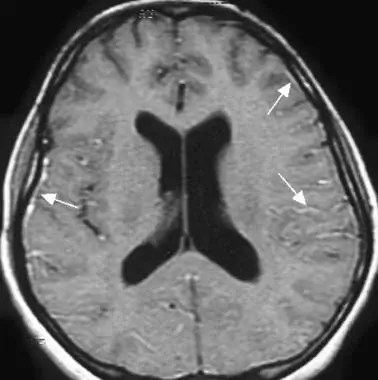

Akute Meningitis; Quelle. eMedicine